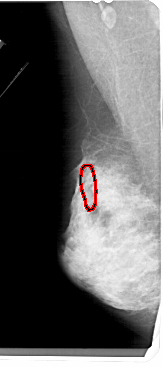

FILE: A_1538_1.LEFT_CC.OVERLAY

TOTAL_ABNORMALITIES 1

ABNORMALITY 1

LESION_TYPE CALCIFICATION TYPE PUNCTATE DISTRIBUTION SEGMENTAL

ASSESSMENT 4

SUBTLETY 2

PATHOLOGY MALIGNANT

TOTAL_OUTLINES 1

BOUNDARY

LEFT_CC LINES 5056 PIXELS_PER_LINE 2146 BITS_PER_PIXEL 12 RESOLUTION 43.5 OVERLAY